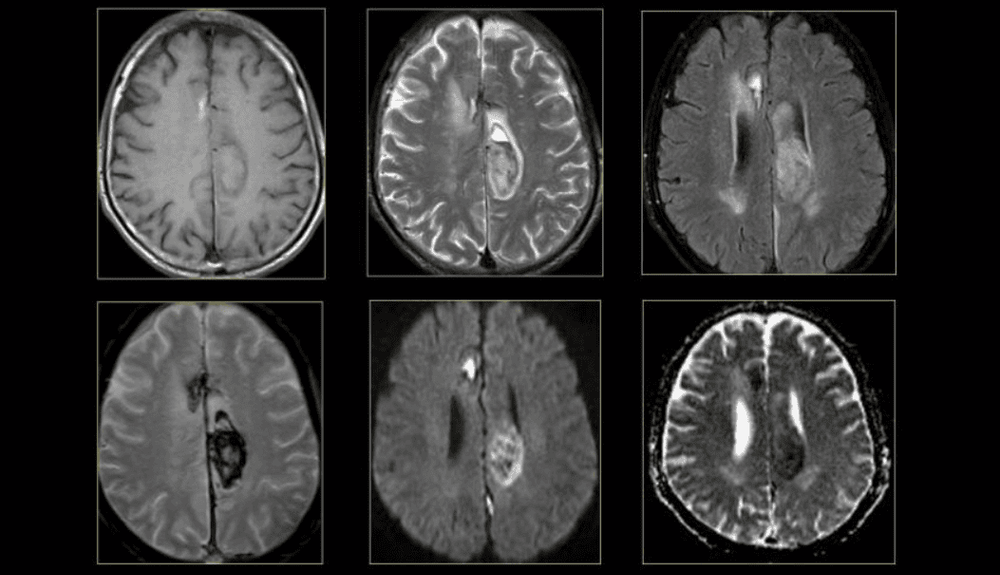

Thực tế, cộng hưởng từ (MRI) thường quy sử dụng proton H+ trong nước để tạo hình, trong khi đó cộng hưởng từ phổ sử dụng các chất chuyển hóa chứa P, Na, K, C, N, F để đánh giá nồng độ các chất chuyển hóa, cộng hưởng từ phổ thu được phổ với các đỉnh tương ứng là nồng độ các chất trong vùng khảo sát. Các quá trình bệnh lý liên quan đến sự thay đổi các chất chuyển hóa này.

Các bước cơ bản trong khảo sát cộng hưởng từ phổ là lấy mẫu đo, định vị vùng đo, chọn chuỗi xung với thời gian TE, khối thể tích phù hợp và thu nhận phổ. Kết quả của cộng hưởng từ phổ được phân tích thành đường dạng biểu đồ phổ. Mỗi đỉnh của phổ đặc trưng bởi tần số, chiều cao, độ rộng và diện tích, chiều cao hoặc diện tích vùng bên dưới đỉnh tượng trưng cho nồng độ tương đối của chất chuyển hóa. Mỗi chất đều có vị trí nhất định trên phổ, tùy tần số tiến động. Các chất chuyển hóa cơ bản thường được ghi hình trên phổ là choline, Creatine, NAA, Lactate.

Cộng hưởng từ phổ giúp đánh giá các chất chuyển hóa như Lac (Lactate) gây nhồi máu não cấp

– NAA (N-Acetylaspartate): Là chất chỉ điểm về mật độ và khả năng sống còn của sợi trục và tế bào thần kinh. NAA giảm trong hầu hết các trường hợp tổn thương não.

– Cr (Creatine): Là chất chỉ điểm cho chuyển hóa năng lượng ở mô não. Cr giảm trong u não, nhiễm trùng, hoại tử , xơ cứng não rải rác cấp…

– Cho (Choline): Là thành phần chuyển hóa phospholipid và là chất chỉ điểm của tăng sinh màng tế bào do u. Cho tăng cao trong u, chấn thương, viêm nhiễm, tăng áp lực thẩm thấu, mất myelin…

– Lac (Lactate): Là chất chỉ điểm các quá trình chuyển hóa đường kỵ khí. Lac tăng cao trong não úng thủy, giảm hay tăng thông khí, giảm oxy não, nhồi máu não cấp và bán cấp, hoại tử, tổn thương dạng nang, áp xe, u, mất myelin, các rối loạn chuyển hóa ty lạp thể.